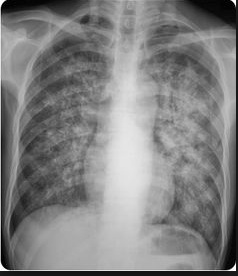

Hilar calcifications: on Xray

coughing: pneumonia

lung with cannon balls: Chest X-ray has patchy alveolar infiltrates/haziness

cannon balls in lung: Lesions or cavities in lungs

lung wall holes, bricks caved in/out: Radiographic images may show either nothing or cavities and/or nodules.